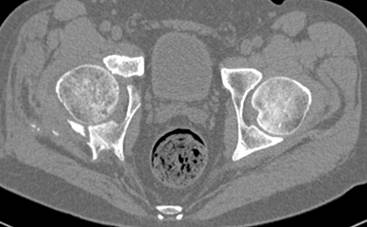

высылаю дополнительно сканы.

итак, второй вариант: высокий двухколонный с вовлечением КПС... Ни одно из основных повреждений не репонировано, кроме задней стенки. Скорее всего попытка реконструкции вертлуги сейчас будет очень травматичной и не очень эфективной, т.е. вероятный риск более значим, чем ожидаемая польза... Лучше подождать, и потом сразу эндопротез

подождать сколько, чего? такая дыра в задней колонне не закроется никогда.

потом эндопротез какой? в такой ситуации приходит на ум Burch-Schneider cage, в 35 лет, дальше что делать?